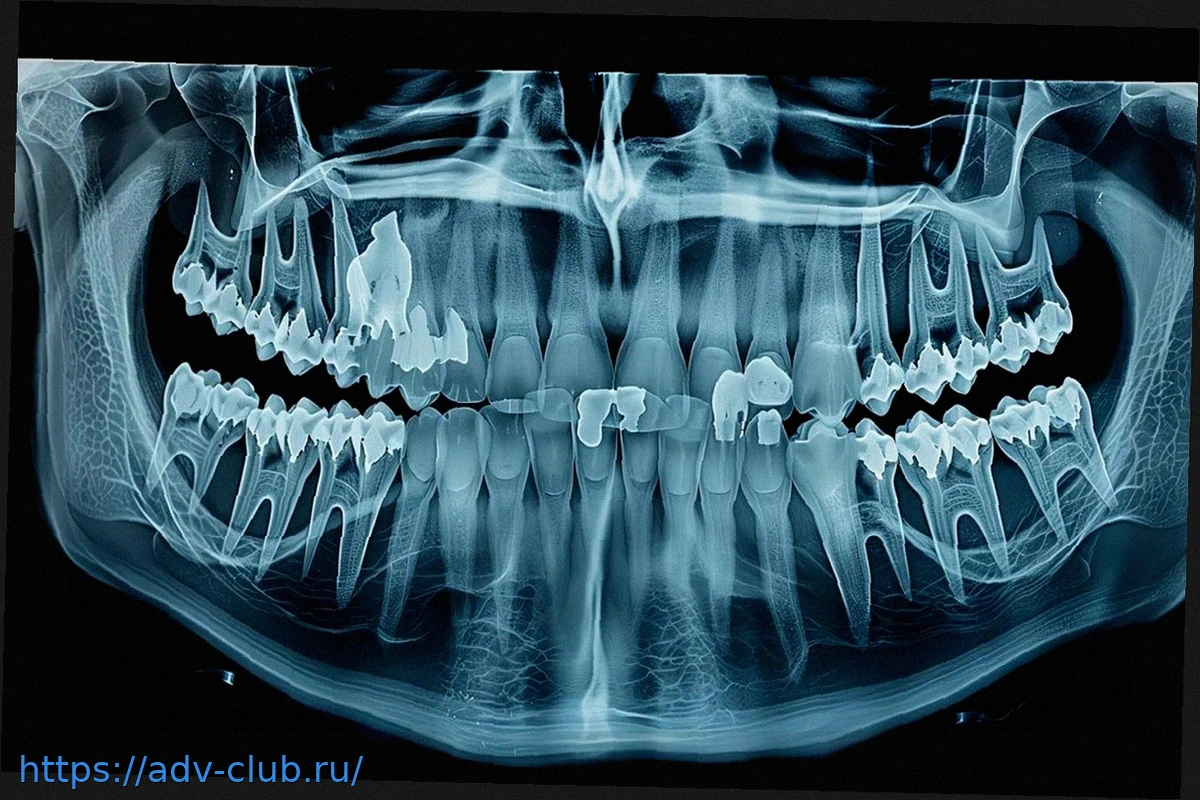

Una tomografía computarizada de una momia perteneciente a la cultura Pazyryk, descubierta en la región de Altái, ha revelado una «prótesis» mandibular innovadora para su época. Este estudio muestra que se utilizaron materiales como crin de caballo o tendones para estabilizar la mandíbula después de una lesión grave, un testimonio impresionante de la medicina antigua hace aproximadamente 2.500 años.

Hallazgo sorprendente en Siberia: una momia de 2.500 años con una prótesis mandibular avanzada